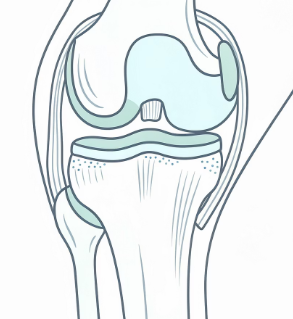

무릎은 몸무게를 지탱하면서 걷기, 뛰기, 앉기 같은 동작을 반복적으로 수행하는 관절입니다.

이 중에서도 무릎 안쪽은 체중 부하가 집중되기 쉬운 구조로 되어 있어 부담이 쉽게 쌓입니다.

무릎 관절 안쪽에는 충격을 흡수하는 반월상연골이 위치해 있습니다.

무릎 안쪽을 지지하는 내측 인대가 늘어나거나 손상되면 통증이 발생합니다.